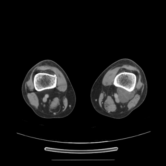

The category discovery clusters employing our LDPO method are found to be more visually coherent and cluster-wise balanced in comparison to the results in [44] where clusters are formed only from text information ( radiology reports). Fig. 4 Left shows the image numbers for each cluster from the AlexNet-FC7-Topic setting. The numbers are uniformly distributed with a mean of 778 and standard deviation of 52. Fig. 4 Right illustrates the relation of clustering results derived from image cues or text reports [44]. Note that there is no instance-balance-per-cluster constraints in the LDPO clustering. The clusters in [44] are highly uneven: 3 clusters inhabit the majority of images. Fig. 5 shows sample images and top-10 associated key words from 4 randomly selected clusters (more results in the supplementary material). The LDPO clusters are found to be semantically or clinically related to the corresponding key words, containing the information of (likely appeared) anatomies, pathologies (e.g., adenopathy, mass), their attributes (e.g., bulky, frontal) and imaging protocols or properties.

Next, from the best performed LDPO models in Table 2, AlexNet-FC7-Topic has Top-1 classification accuracy of 0.8109 and Top-5 accuracy 0.9412 with 270 formed image categories; AlexNet-FC7-ImageNet achieves accuracies of 0.8099 and 0.9547, respectively, from 275 discovered classes. In contrast, [44] reports Top-1 accuracies of 0.6072, 0.6582 and Top-5 as 0.9294, 0.9460 on 80 text only computed classes using AlexNet [27] or VGGNet-19 [47], respectively. Markedly better accuracies (especially on Top-1) on classifying higher numbers of classes (being generally more difficult) highlight advantageous quality of the LDPO discovered image clusters or labels. This means that the LDPO results have rendered significantly better performance on automatic image labeling than the most related previous work [44], under the same radiology database. After the subjective evaluation by two board-certified radiologists, AlexNet-FC7-Topic of 270 categories and AlexNet-FC7-ImageNet of 275 classes are preferred, out of total six model-encoding setups. Interestingly, both CNN models have no deep feature encoding built-in and preserve the gloss image layouts (capturing somewhat global visual scenes without unordered FV or VLAD encoding schemes [9, 8, 21].).

The final trained CNN classification models allow to compute the pairwise category similarities or affinity scores using the CNN classification confusion values between any pair of classes (Sec. 3.5). Affinity Propagation algorithm is called recursively to form a hierarchical category tree. The resulted category tree has (270, 64, 15, 4, 1) different class labels from bottom (leaf) to top (root). The random color coded category tree is shown in Fig. 6. The high majority of images in the clusters of this branch are verified as CT Chest scans by radiologists. Enabling to construct a semantic and meaningful hierarchy of classes offers another indicator to validate the proposed LDPO category discovery method and results. Refer to the supplementary material for more results. We will make our trained CNN models, computed deep image features and labels publicly available upon publication.